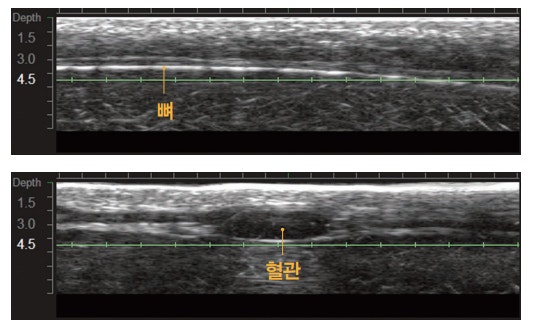

그리고 울쎄라는 슈링크와는 다르게 실시간으로

피부 속을 직접 확인하며 뼈와 혈관을 피해

시술할 수 있다는 점입니다.

직접 볼 수 있다는 것은 집속된 에너지를

뼈나 혈관, 또는 성형이나 필러 시술 등으로 인해

발생한 보형물 또는 삽입물을 피할 수 있다는

것이며, 눈가와 같이 얇은 피부층이나 턱이나

볼과 같이 두꺼운 피부층을 모두 고려하여

타겟팅 할 수 있다는 점입니다.

그리고 피부에 팁이 닿아야만 피부 속을 확인할 수

있는 만큼 피부와 팁의 미접촉 문제로 발생할 수

있는 시술의 부작용(화상 등)을 예방할 수 있습니다.

또한 피부와 팁이 정확하게 닿아야

피부층이 초음파 화면에서 매끄럽게 나오는데

매샷마다 이 화면이 깨끗하게 보이지 않으면

시술하지 않기 때문에 시간이 매우 오래 걸립니다.

그만큼 한샷한샷 정확하게 시술을 한다고 할 수 있습니다.